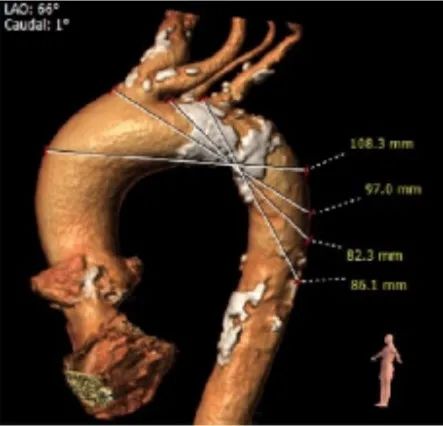

冠脉高度测量:

LEFT CORONARY

左冠开口高度16.0mm

RIGHT CORONARY

右冠开口高度17.0mm

外周血管及主动脉弓解剖:

入路血管扭曲,双侧血管内径良好,所见主动脉血管壁显著钙化。